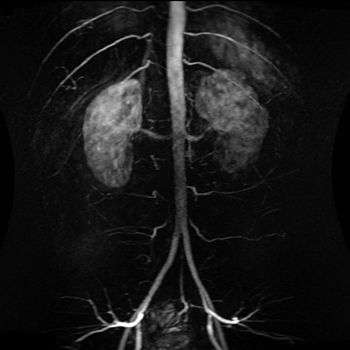

![]() The abdominal aorta and its branches. | |

Abdominal aorta